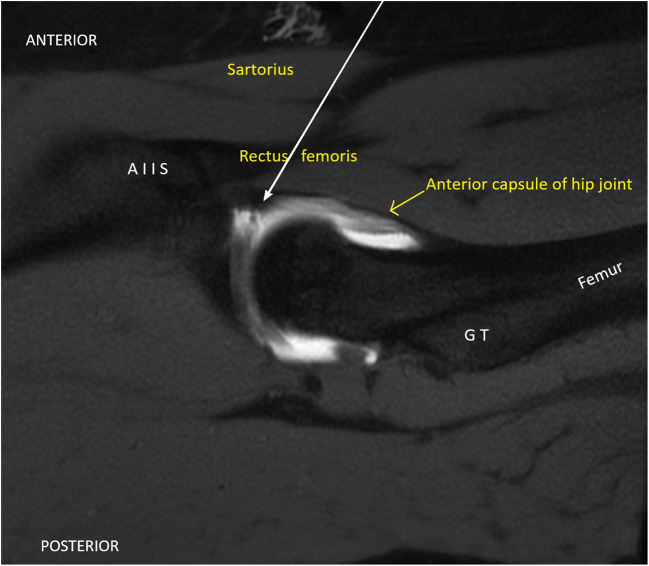

Fig. 1.

Sagittal MRI image with solid white arrow showing the pathway of the anterior portal of hip arthroscopy through the sartorius, rectus femoris, and then entering the anterior capsule of the hip joint. (AIIS anterior inferior iliac spine, GT greater trochanter)

The hip joint is enveloped by a capsule which is attached to the rim of the acetabulum and the neck of femur. Three main ligaments which strengthen the capsule–ligamentous complex include iliofemoral, ischiofemoral, and pubofemoral ligaments. Standard hip arthroscopy portals include an anterolateral portal (just anterior to the tip of the greater trochanter), posterolateral portal (posterior to the tip of the greater trochanter), and an anterior portal (lateral and distal to the intersection of a line drawn transversely from the greater trochanter and a line drawn distally from the ASIS) [3]. The pathway of the anterior portal penetrates the muscle belly of the sartorius and the rectus femoris before entering the anterior capsule of the hip joint (Fig. 1). The anterior portal has been described with several variations as injury to the lateral femoral cutaneous nerve is a potential associated complication.